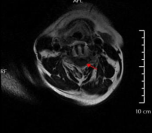

术后复查显示内固定位置良好、椎管减压充分,患者自觉症状明显缓解

为确保手术成功,骨科二区专家团队与湘雅三医院苗惊雷教授紧密协作,在麻醉科和手术室的配合下,成功为患者实施颈前路椎间盘切除术+椎管扩大减压术+植骨融合内固定术,患者术后即感四肢肌力明显改善,目前恢复良好,已顺利出院。